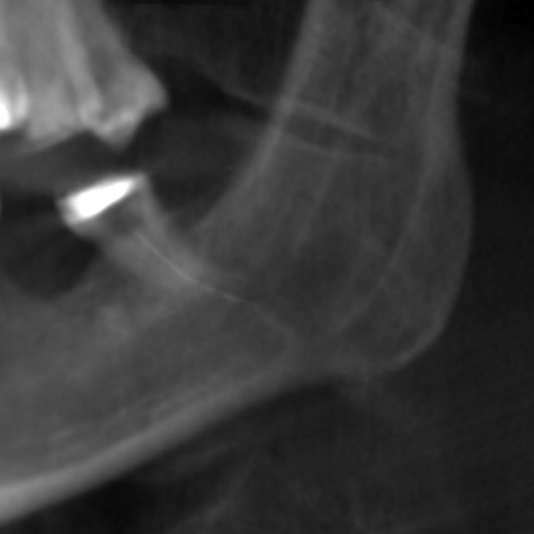

The patient’s symptoms and the close proximity of the broken instrument to the mandibular canal seen in panoramic radiography suggested that the broken endodontic instrument was in contact with the IAN. To confirm this diagnosis, CBCT examination was undertaken, and clearly showed the broken instrument in the periapical area of the mandibular left third molar and that the instrument was inside the mandibular canal. The result was the same as the panoramic examination, broken instrument was noted in the left mandibular canal Figure 3a, Figure 3b.

Figure 3b.CBCT examination broken endodontic instrument lodged in the mandibular canal.